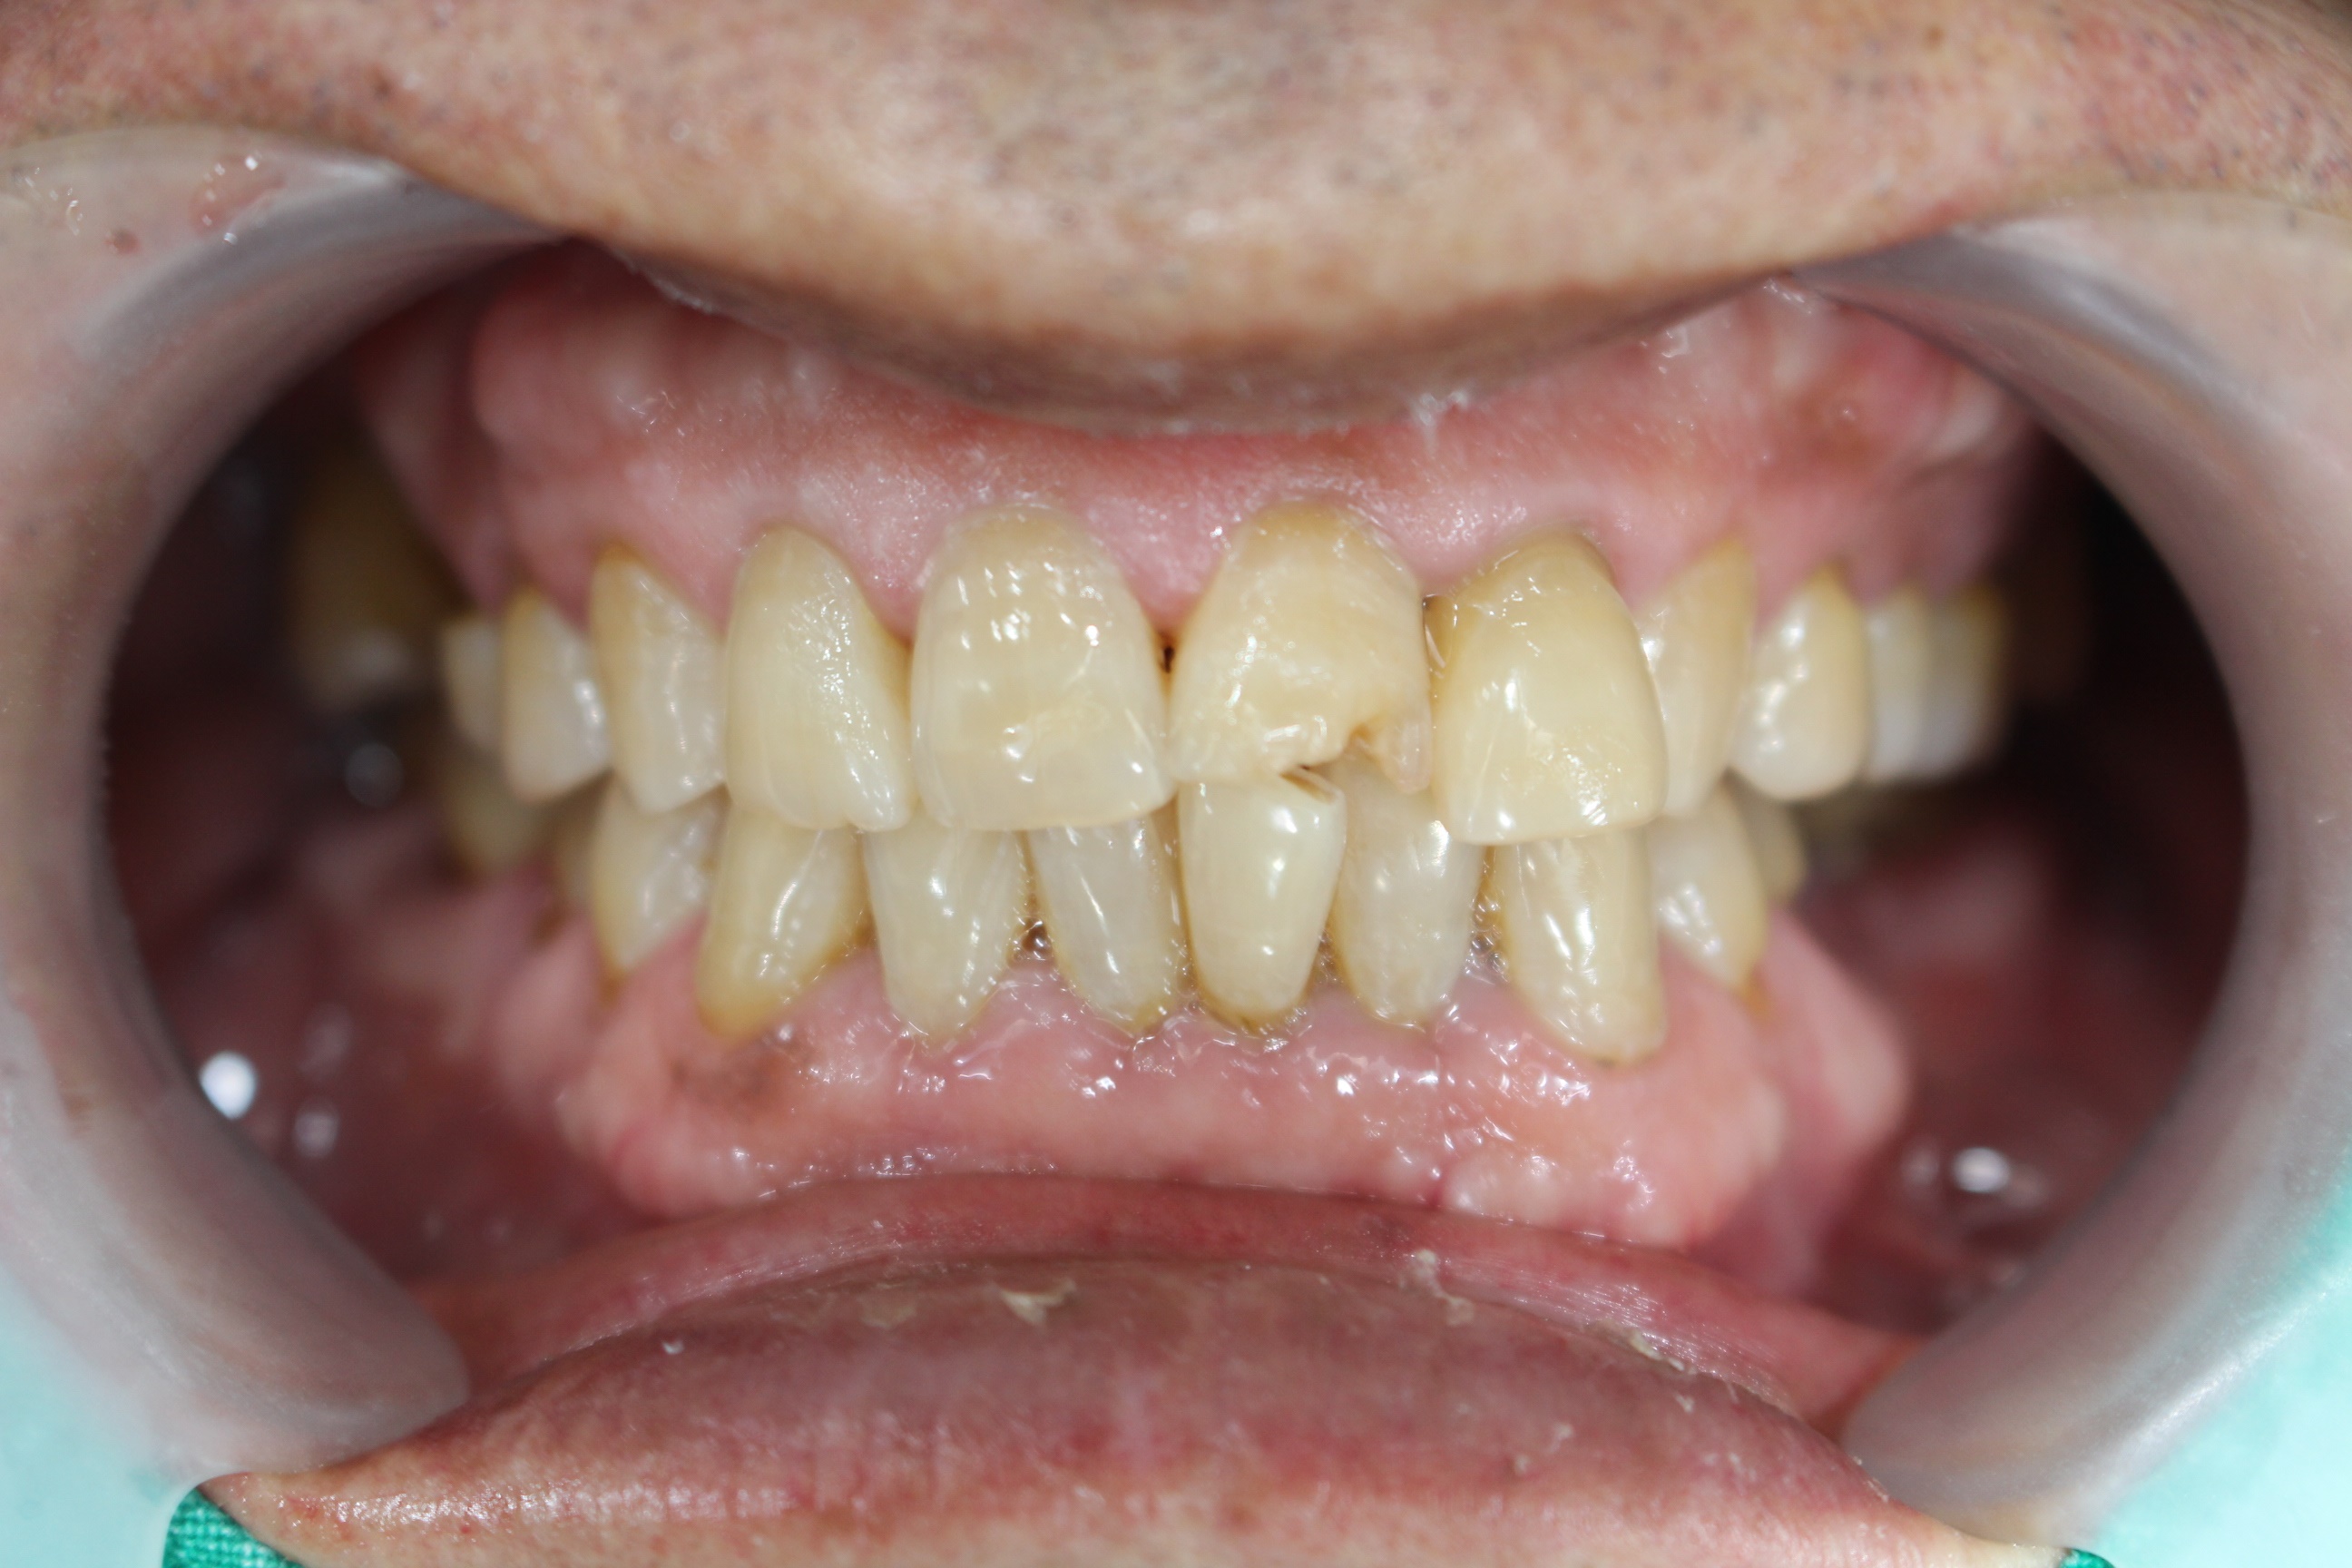

수술 전

수술 후

구치부 임플란트 식립사례

전후사진